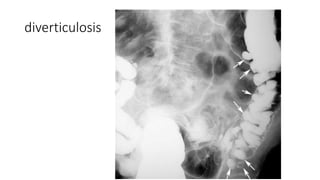

• Enfermedad diverticular

• Diagnostico, valoracion y complicaciones

• Radiografia simple: absceso pelvico con gas

• Colon por enema: diverticulos, alteraciones de mucosa, hipertrofia muscular,

espasmo, disminucion de caliber, fijacion de segment

• TC: diverticulos (saculaciones), hipertrofia muscular, proceso inflamatorio de

grasa pericolica

diverticulosis

Enfermedades inflamatorias einfecciones • Colitis ulcerative cronica inespecifica • Colon por enema: engrosamiento mucoso, perdida de aspecto liso y suave, ulceraciones superficiales finas, ulceras en boton de camisa • TC: engrosamiento (doble halo o tiro al blanco) • Enfermedad diverticular • Diagnostico, valoracion y complicaciones • Radiografia simple: absceso pelvico con gas • Colon por enema: diverticulos, alteraciones de mucosa, hipertrofia muscular, espasmo, disminucion de caliber, fijacion de segment • TC: diverticulos (saculaciones), hipertrofia muscular, proceso inflamatorio de grasa pericolica